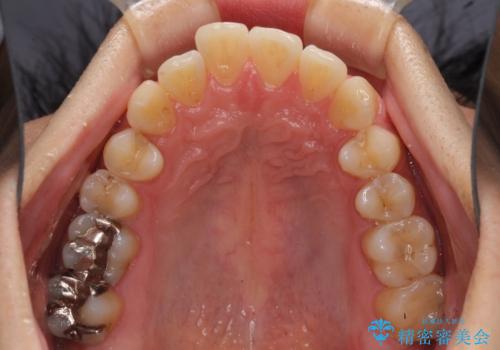

インビザライン・ライトによる矯正治療の後戻り改善

- 矯正治療の後戻りを気にして来院された患者様です。

後戻りは軽微でしたので、インビザライン・ライトにより矯正治療を行うこととしました。